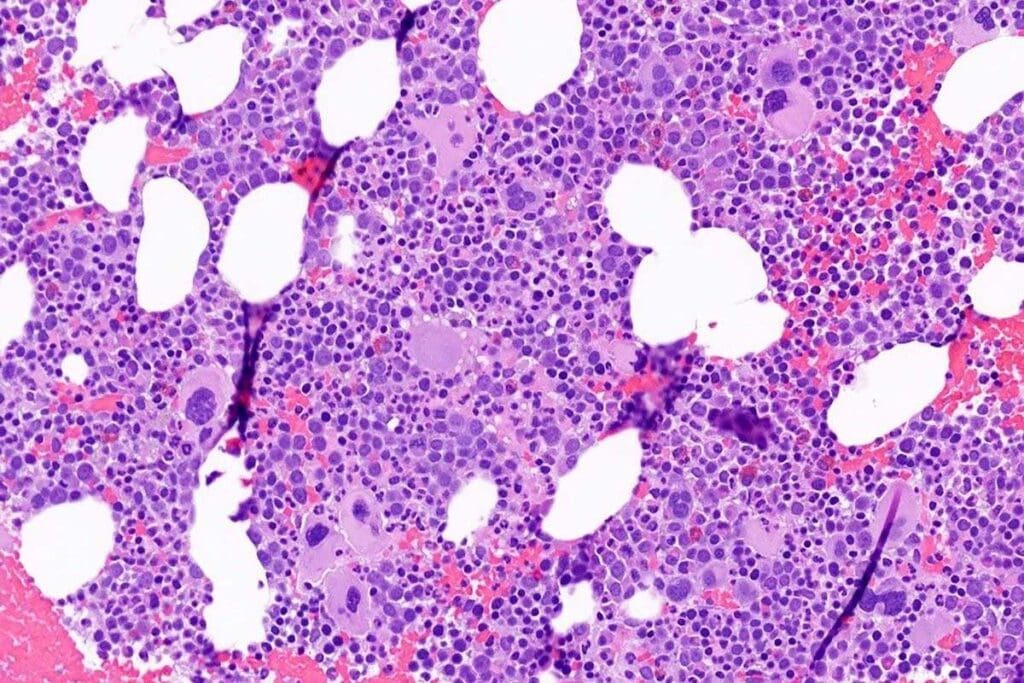

Bone Marrow Biopsy

A bone marrow biopsy is a key test for aplastic anemia. It takes a sample from the hipbone for checking. This test looks at the bone marrow’s cells and if there are any odd ones.